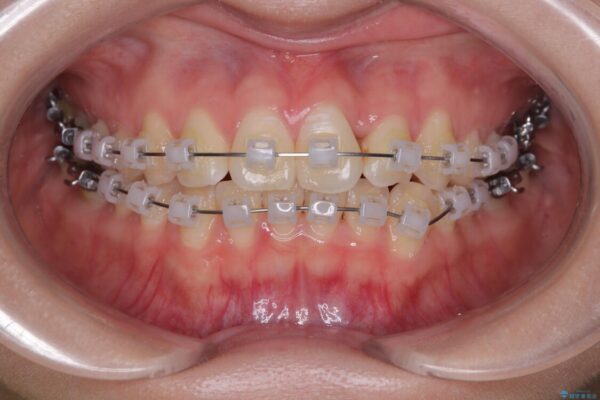

治療途中

• 前歯のねじれ・ガタガタを10か月で改善!20代女性の矯正治療|クリアブラケットでむし歯になりにくい歯並びへ改善 治療途中画像

診察の結果、上下の前歯部に**叢生(そうせい/歯のガタガタ・重なり)**が認められました。

特に上の前歯にはねじれや重なりがあり、審美的にも清掃性にも影響している状態でした。

治療方法としては、装置の目立ちにくさと費用面のバランスを考慮して、プラスチック製のクリアブラケットとメタルワイヤーを組み合わせた矯正装置を使用することにしました。